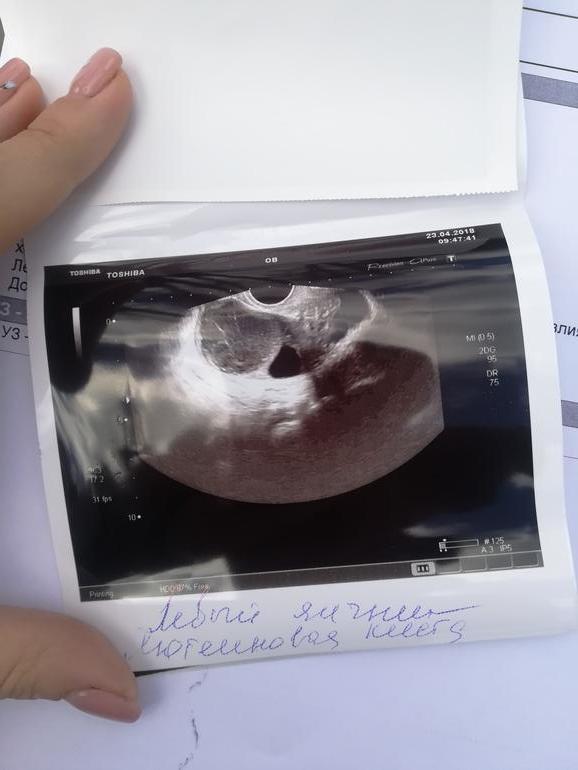

Девочки, помогите разобраться,я совсем запуталась. На 16 ДЦ дф был 21 мм, сегодня 19 ДЦ, сказали киста лютеиновая, но график бт говорит что овуляция была. Если есть лютеиновая киста то была овуляция или нет? И что с ней делать, сегодня к врачу попасть нет возможности. Фото и заключение прилагаю

по фото похоже на лнф, в таком случае фоллик лопнул внутрь себя без выхода яйцеклетки, но это от узи зависит, может сфоткали в неподходящий момент... смущает в описании наличие капсулы 1,5 мм - это что? при лнф график 2х фазный и узи картина 2 й фазы

При лютеиновой кисте фолликул не лопается, он просто лютеинизируется. БТ при такой кисте чаще всего соответствует второй фазе цикла.